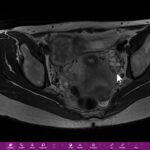

Antes de saber o que é pólipo endometrial, vou dizer para vocês o que é endométrio. O endométrio é aquela camada interna do útero. É ele que prolifera e que se transforma na menstruação durante o período menstrual.

Às vezes, o endométrio se dobra formando como se fosse uma língua ou um pólipo endometrial. Essa pequena dobra endometrial pode causar hemorragias. A mulher às vezes está tendo hemorragia e não tem miomas, mas ela tem isso. O pólipo endometrial está causando hemorragia e pode causar também escapes vaginais.

Em alguns casos, o pólipo endometrial pode ser acompanhado. Ou seja, através de uma ultrassonografia transvaginal e de acompanhamento normalmente ele não cresce. Se começa a crescer, a gente tem que retirar o que pode ser um câncer de útero.